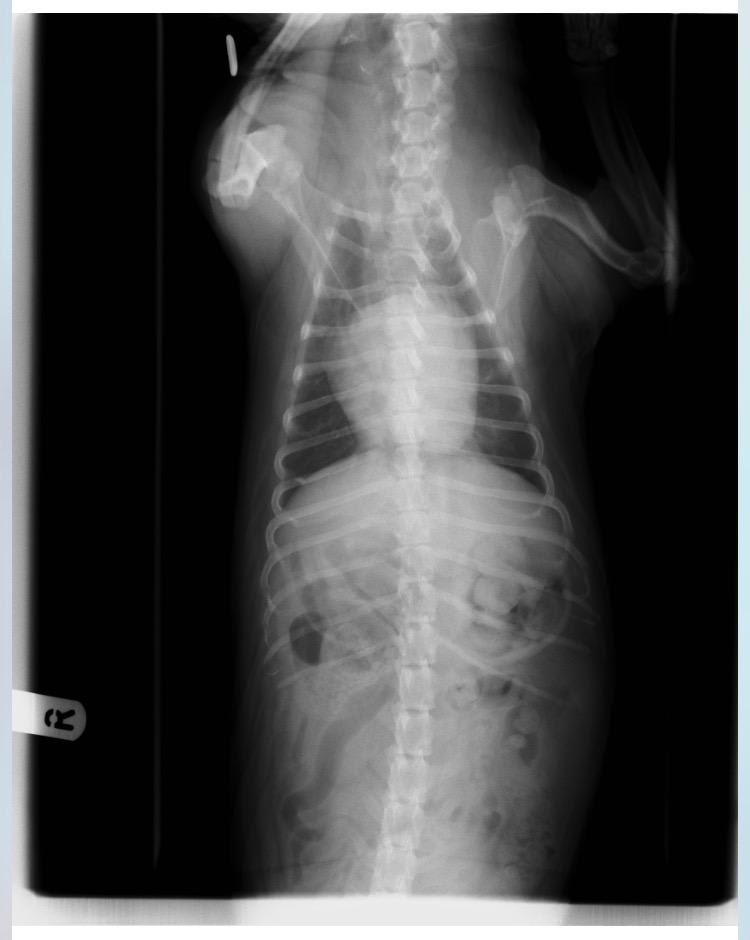

I agree that Duke heart looks enlarged and it is pushing up on his trachea. I cannot diagnose his condition without doing an exam but with just looking at the X-rays, I would say he definitely has a heart condition. I have heard coughs from heart problems sound very similar to upper respiratory infections. Your vet will be able to put him in some heart medicine to help him. Heart medicine will slow down the progression of heart disease and help him feel better. I hope this helps. I'm sorry for the news!

Coughing can indeed be caused by kennel cough infection but it can also be caused by heart disease. In the above radiography the heart looks enlarged and seems to be pushing up the trachea. This can lead to trachea sensitivity which can cause a bad cough. A diagnosis of heart disease is made on clinical signs, listening to the chest along with diagnostic imaging. I would imagine that your vet is correct in this instance. Treatment involves administering tablets to increase the heart output, control fluid in the chest and control kidney involvement. Your vet will be able to make you a treatment plan.